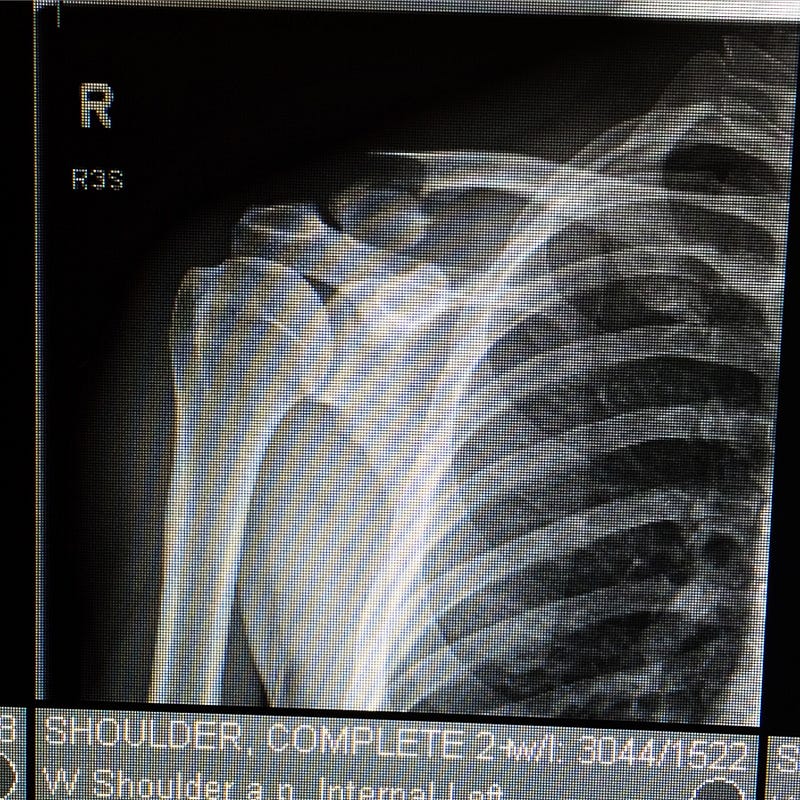

See, I have what’s called a Type 2b distal clavicle fracture. It’s a special kind of beast you’ve got to love when the article I just linked to begins with:

Less-than-stellar grammar aside, further reading doesn’t put me at ease regarding my chances for a full and expedient recovery without surgery. According to these guys, I have a 30–45% non-union rate without going bionic.